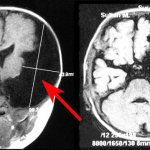

• – различные функциональные и органические заболевания нервной системы, сопровождающиеся повышенной возбудимостью, эмоциональной нестабильностью, снижением умственной работоспособности, памяти и нарушением сна: неврозы, неврозоподобные состояния и вегето-сосудистая дистония, стрессовые нервные расстройства, последствия нейроинфекций и черепно-мозговой травмы, перинатальные и другие формы энцефалопатий (в т.ч. алкогольного генеза);